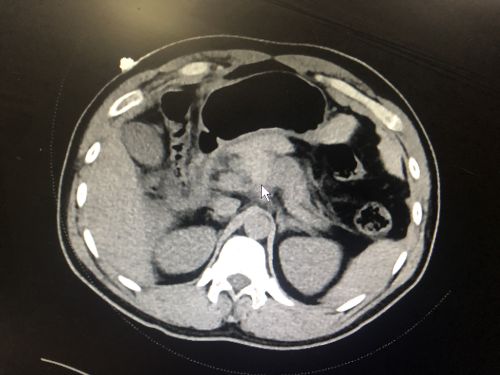

ct显示胰腺损伤出血(鼠标位置)。

入院体查发现,患者全腹压痛、反跳痛、腹肌紧张,头部、胸部、全腹部CT提示:胰腺断裂,胰腺颈体部及小网膜囊、腹腔积血,盆腹腔积液。医生对其病情展开讨论,考虑为“胰腺断裂并腹腔内出血”,须立即进行急诊手术。

术中发现,患者胰腺颈部靠近胰体部有大量血凝块,腹腔内积血约1000ml, 导致术野显示困难。成伟主任指示,采用荧光显影技术为手术术野显影,发现患者胰腺颈部完全断裂,进一步判断残端胰腺血运情况,并根据显像情况切除血运不良坏死的胰腺组织。这一技术的使用不仅帮助手术医生准确判断脏器受损情况,还大大减少了术后胰漏、肠漏、出血等并发症的发生几率。